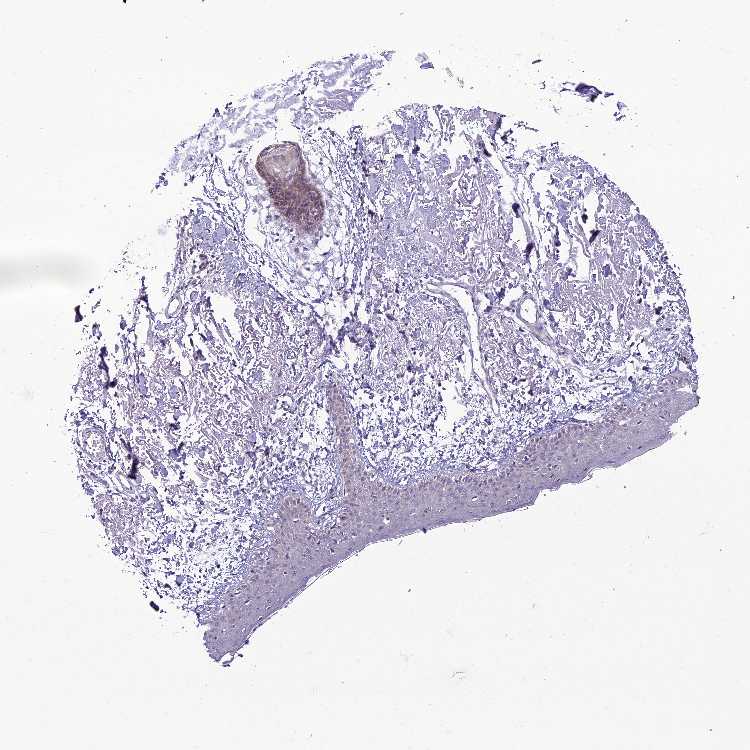

SKIN 1 - Antibody stainingi

Antibody staining in the annotated cell types in the current human tissue is reported as not detected, low, medium, or high, based on conventional immunohistochemistry profiling in selected tissues. This score is based on the combination of the staining intensity and fraction of stained cells.

Each image is clickable and will lead to virtual microscopy that enables deeper exploration of all samples and also displays staining intensity scores, fraction scores and subcellular localization as well as patient and tissue information for each sample.

Antibody HPA044621

Langerhans Not detected

Fibroblasts Not detected

Keratinocytes Not detected

Melanocytes Not detected